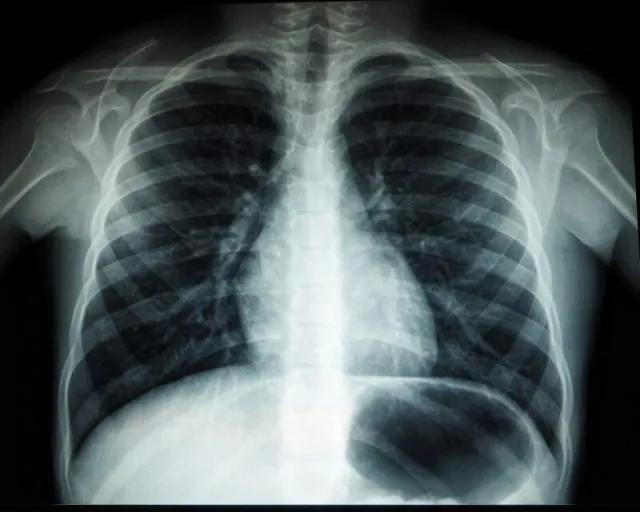

Z outsourcingiem różnego rodzaju usług można spotkać się w dzisiejszych czasach także jeśli chodzi o branżę medyczną. Przykładem takiej usługi jest chociażby teleradiologia, która pozwala, na zlecenie konkretnej jednostki medycznej, zdalnie ocenić i opisać badania obrazowe. Na czym jednak konkretnie polega taka usługa i jakie są korzyści z jej zastosowania?

Zasadniczo rzecz biorąc, teleradiologia nie różni się wiele od innych usług outsourcingowych. Szpital, czy inna jednostka medyczna, nawiązuje współpracę z usługodawcą, takim jak na przykład https://telediag.pl/, któremu zlecane będzie wykonywanie opisów przeprowadzonych w tejże jednostce badań. Za pomocą specjalnego systemu szpitale i przychodnie lekarskie przesyłają wykonane przez siebie obrazy diagnostyczne, zlecają ich opisy, ustalają priorytet i nie tylko. Całość jest bardzo prosta i intuicyjna. Oczywiście opis każdego badania znajdującego się w systemie, szpitale mogą też wykonać samodzielnie.

Opisy takich badań wykonywane są przez doświadczonych radiologów, w trybie, jaki zaleciła dana jednostka medyczna. Tego typu outsourcing usług pozwala przygotować specjalistyczny opis obrazów diagnostycznych w szybki sposób, w praktyce z dowolnego miejsca w Polsce. Teleradiologia pozwala znacząco zoptymalizować czas niezbędny do uzyskania profesjonalnego opisu, a jednocześnie znacząco odciążyć radiologów pracujących w danej jednostce medycznej.